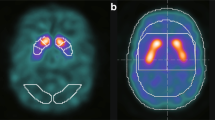

The intensity normalization step is essential, as it corresponds to the initial step in any subsequent computer-based analysis. In this work, a proposed intensity normalization approach based on a predictive modeling using multivariate linear regression (MLR) is presented. Different intensity normalization parameters derived from this model will be used in a linear procedure to perform the intensity normalization of 123 I-ioflupane-SPECT brain images. This proposed approach is compared to conventional intensity normalization methods, such as specific-to-non-specific binding ratio, integral-based intensity normalization and intensity normalization by minimizing the Kullback-Leibler divergence. For the performance evaluation, a statistical analysis is used by applying the Euclidean distance and the Jeffreys divergence. In addition, a classification task using support vector machine to evaluate the impact of the proposed methodology for the development of a computer aided diagnosis (CAD) system for Parkinsonian syndrome detection.